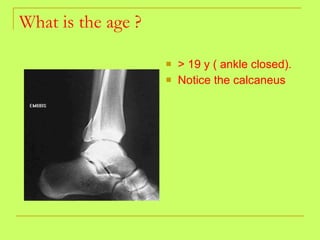

What is the age ? > 19 y ( ankle closed)

What is the age ? > 19 y ( ankle closed). Notice the calcaneus

Age from lower limb examination 1) Lesser trochanter  (16y )-----Greater trochanter  (17y)  ------ Head of the femur  (18y). 2) Lower end of the femur + shaft  (21y). 3) Upper end of the tibia +shaft  (21y). 4) Lower end of the tibia +shaft  (18 y).   By foot examination ossific center appears at calcanium at  6 years  and union of epiphysis at the calcanium at  14 years  ,so examining only this bone gives us a range of 8 years